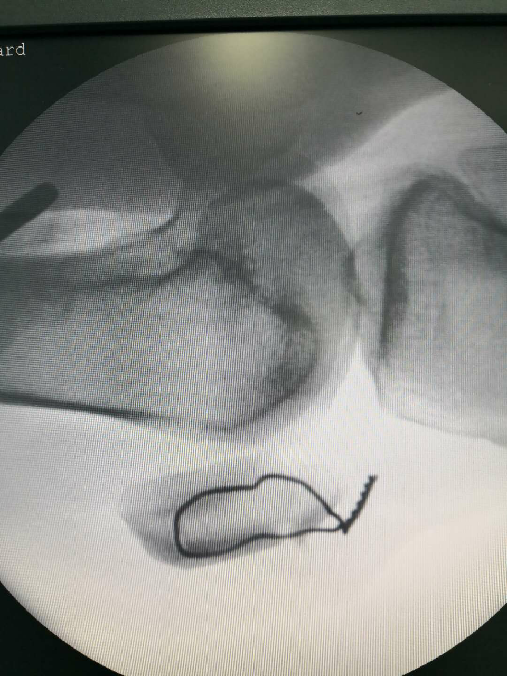

点氏复位钳经皮复位打入一克氏针临时固定

用电钻在髌骨上下极打一骨洞,用腰穿针带过钢丝

紧贴钢丝上方打入两髌骨针

折断髌骨针后再次收紧钢丝

术中照